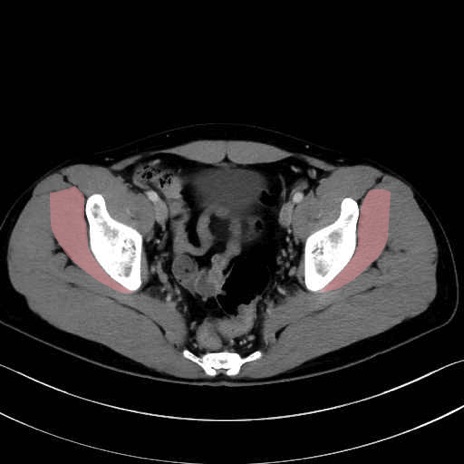

小殿筋 (Gluteus minimus)